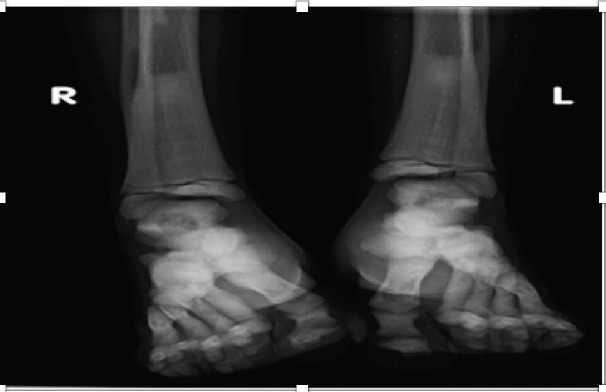

Case presentation: The patient is an eight-year-old girl who came to our hospital with complaints of bilateral arm swelling and visual disturbances for four years and a history of fracture of the left lower extremity two years before presentation. Physical examination revealed nontender bilateral arm swelling and a shorter left leg. The laboratory tests were within normal limits. A skeletal radiograph showed typical radiographic features of osteopetrosis.